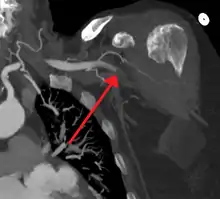

![]() انصمام حاد في الشريان الفخذي الأيمن مُسببًا نقص التروية انصمام حاد في الشريان الفخذي الأيمن مُسببًا نقص التروية | |